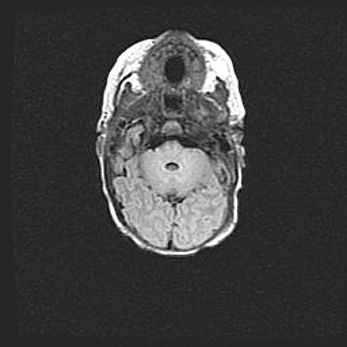

Неполная лизэнцефалия (пахигирия). Открытая гидроцефалия.

Возраст: 17 дней

Вес: 3110 г

Пол: мужской

Окружность головы: 33,5 см

Срок гестации: 35-36 недель

Лизэнцефалия—недоразвитие корковой пластинки и мозговых извилин в результате нарушения миграции нейронов коры. Поверхность мозговых полушарий гладкая. Микроскопически выявляется отсутствие нормальных слоев коры и скопление групп нейронов в подкорковом белом веществе.

Пахигирия—уменьшение числа вторичных извилин. В пораженном полушарии нервные клетки образуют толстый недифференцированный слой с неправильно расположенными нервными волокнами и группами гетеротопных клеток. Нервные клетки незрелые. Белое вещество истончено. При этом нередко аномально развит корково-спинномозговой путь.